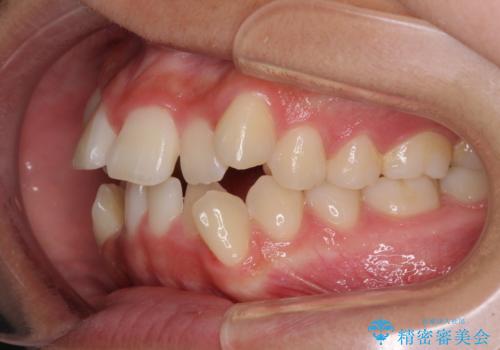

上顎骨幅が狭い 急速拡大装置を併用した抜歯矯正

- 歯列全体の叢生を気にして来院された患者様です。

検査を行った結果、上顎骨の横幅が相対的に狭いことが分かり、叢生が強いことから、急速拡大装置にて上顎骨を側方に拡大することで、叢生の解消と奥歯の咬み合わせ改善を図ることとしました。

一般的には上下左右の第一小臼歯4本を抜歯する必要がありますが、拡大量によっては非抜歯矯正の適用となる可能性があるため、まずは非抜歯矯正で治療を開始し、抜歯が必要と判断された時点で速やかに4本抜歯を行うこととしました。

急速拡大後、歯列はきれいに並んだのですが、口元が出っ歯になってしまったため、速やかに抜歯を行い、治療期間がいたずらに遅延することのないようにしました。